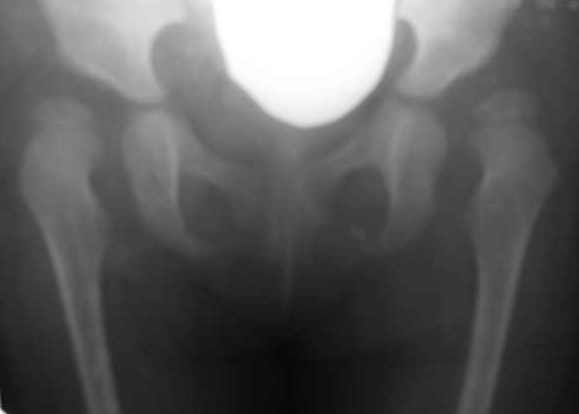

Дисплазия тазобедренного сустава у девочки 2х лет.

Из анамнеза: в 10 месячном возрасте поставлен диагноз врожденного вывиха бедер. Лечилась консервативно на данный момент. Рг-картина неудовлетворительная. Посоветуйте, пожалуйста тактику оперативного лечения.

Na snimke mild dysplasia, hughe sleva, no est isprava.

V2,4 goda nelsya prosto vpravlyat bez ukorochenia bedra-inache poluchite AVN.Net nadobnosti delat varus-Neck shaft angle uetih detei mormalnyi.Vvashem sluchae mne kaghetsya net smysla delat open reduction-po moemu idealno budet proizbesti -shortening,derotation 20-30 dedrees+Dega/Salter( po vashemu vyboru).posylau vam statyu po teme.

Этого снимка не достаточно чтобы решить что делать дальше. Нужен снимок в отведении и внутренней ротации бедер. Кроме того опишите пожалуйста клиническую картину. Важно где находится головка бедра - в суставе или нет, если нет , можно ли ее вправить при простой манипуляции. Это может быть и ротационный подвывих, тогда это меняет тактику. Короче говоря клиника не менее важна чем рентген.До получения полной информации я думаю что не стоит строить огромные планы потому что может оказаться что удастся обойтись более щадящими методами.